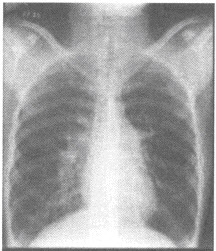

男性,26岁,发育尚可。反复发生上呼吸道感染,近来出现气急,心悸,易疲劳。听诊肺动脉瓣区第二心音亢进,可听到收缩期杂音。行胸部X线平片检查如下图:

A.右室流出道狭窄

B.主动脉瓣关闭不全

C.二尖瓣脱垂

D.房间隔缺损

E.三尖瓣闭锁